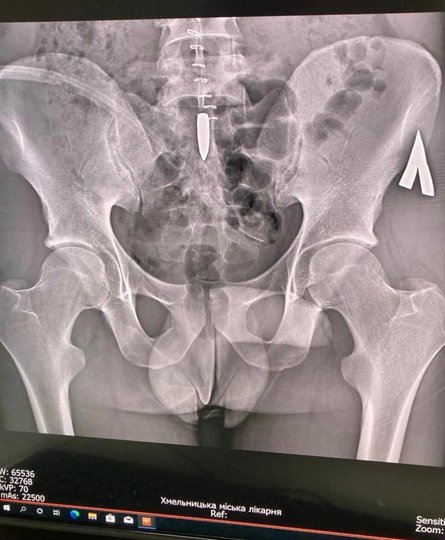

Операція була проведена 8 лютого, повідомляє прес -служби муніципальної лікарні Чмельнистського. Відомо, що 27-річна армія була пострілом під час бійки. ЩоКуля через бічну стінку живота з'явилася і була в поперековому хребті, пронизав постійний мозок, змінив траєкторію вниз і була на рівні 1-2 священних кіл, між нервовими корінням, відповідальними за іннервацію“, Пояснювати в лікарні.

З цієї причини пацієнт був слабким у ногах. Він також мав шкоду внутрішнім органам. Ось чому хірурги вперше здійснили оригінальну хірургічну обробку вогнепального поранення на шлунку з шиттям дефектів внутрішніх органів. Вже після стабілізації нейрохірурги провели складну операцію, під час якої вони витягнули м'яч.

ЩоСкладність хірургічного лікування полягає в тому, що м'яч всередині загортається в так звану “біоплівку”, яка також мала нервові коріння, які виконують важливі неврологічні функції, розмір яких має діаметр 1-2 мм. Після зняття м'яча шиття шиття твердого мозку“, – Повідомлення звучить.